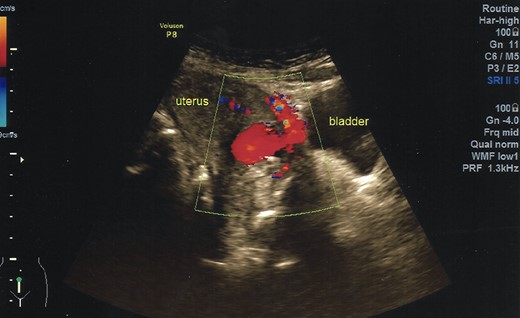

A 40-year-old woman came to the emergency department of the tertiary hospital with vaginal bleeding. She had a history of two cesarean sections (CS), and the last one was 3 years prior without any contraception. She was 10 weeks pregnant and had gone through abnormal uterine bleeding for 2 months. The patient arrived at the emergency department conscious with a blood pressure of 80/40, heart rate of 112 beats/min and hemoglobin level of 11.2 g/dl. Two bags of Ringer’s lactate solution (1000 ml) were given to stabilize the patient. After the patient was stable, a vaginal examination was performed. The cervix was normal, and a small amount of bleeding came out from the external os of the cervix. Ultrasound examination was performed. It showed blood flow in the lower anterior segment of the uterus, but the gestational sac could not be seen, and no intraabdominal bleeding was observed (Fig. 1). However, the pregnancy test pack showed a positive result. The patient underwent observation in the emergency department. At 2 h after admission, the patient underwent profuse vaginal bleeding. The blood pressure was 70/40 with a heart rate of 122 beats/min and decreased hemoglobin level of 6.5 g/dl. The patient consented to undergoing hysterectomy. Laparotomy was performed after hemodynamic stabilization. Intraoperative exploration showed no intraabdominal bleeding. The size of the uterus was normal, no uterine perforation was observed, both adnexa were normal and a bulging mass in the left lower uterine segment was observed without any uterine perforations (Fig. 2). Hysterectomy was performed. The gross specimen indicated a CSP (Fig. 3), which was confirmed by histopathological examination (Fig. 4). The patient received blood transfusion intra- and postoperatively. On Day 3 after surgery, the patient was in good, stable condition and was discharged from the hospital.

Ultrasonography demonstrates a rich blood flow in the lower uterine segment with a normal fundus.